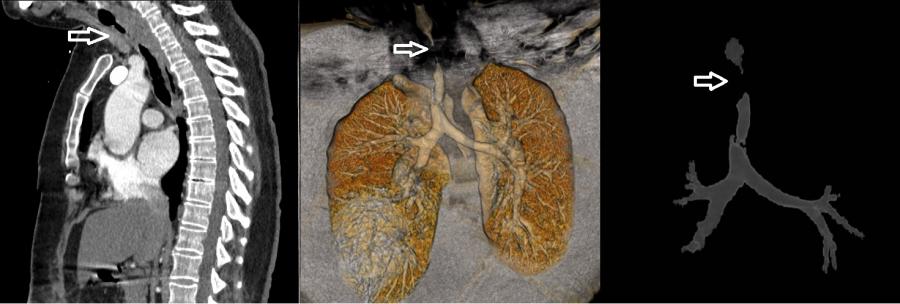

Pandemi döneminde mekanik ventilatör ile solunum desteği alan hasta sayısı artış göstermekle birlikte bu tedaviyi alan hastaların yaklaşık % 5’inde, soluk borusu darlığı durumu gelişebilmektedir. Bu vakalarda kesin tedavi ise cerrahi bir müdahale ile soluk borusunda darlık olan kısmın kesilip çıkarıldıktan sonra sağlıklı iki ucun birbirine dikilmesi yoluyla olmaktadır. KTÜ Farabi Hastanesi’nde, bu vakaların tedavisi, başarılı ve deneyimli bir ekip tarafından üstlenilmektedir.

COVID-19 enfeksiyonu nedeniyle yoğun bakımda mekanik ventilatör ile tedavi görüp taburcu olan 52 yaşındaki kadın hasta, bir ay sonra nefes darlığı şikâyeti ile KTÜ Farabi Hastanesi Göğüs Cerrahisi Polikliniği’ne başvurdu. Yapılan detaylı tetkikler sonucunda hastanın soluk borusunda 4,5 cm uzunluğunda bir daralma tespit edildi. Solunum sisteminin en önemli unsurlarından birisi olan soluk borusunun hava yolunun açılması için acilen Rijit Bronkoskopi yöntemi uygulanarak hastanın soluk borusundaki darlık genişletildi. Hastanın solunumu geçici olarak rahatlatılarak sorunlu bölgenin detaylı olarak teşhis edilmesi sağlandı. Yapılan değerlendirmeler sonucunda, daralan soluk borusu kısmı için iki hafta sonrasına ameliyat planlandı.

Üniversitemiz Farabi Hastanesi Başhekimi Prof. Dr. Celal TEKİNBAŞ liderliğindeki ekip tarafından yapılan ameliyatta, hastanın soluk borusundaki daralmış kısım kesilip çıkarıldıktan sonra sağlıklı uçlar birbirine dikildi. Ameliyat sonrasında sadece 5 gün hastanede yatan hasta, sağlığına kavuşmasının ardından taburcu edildi. Sonraki süreçte, hastanın 10 günlük ve 2 aylık kontrollerinde hastada, hiçbir sorun olmadığı saptandı.